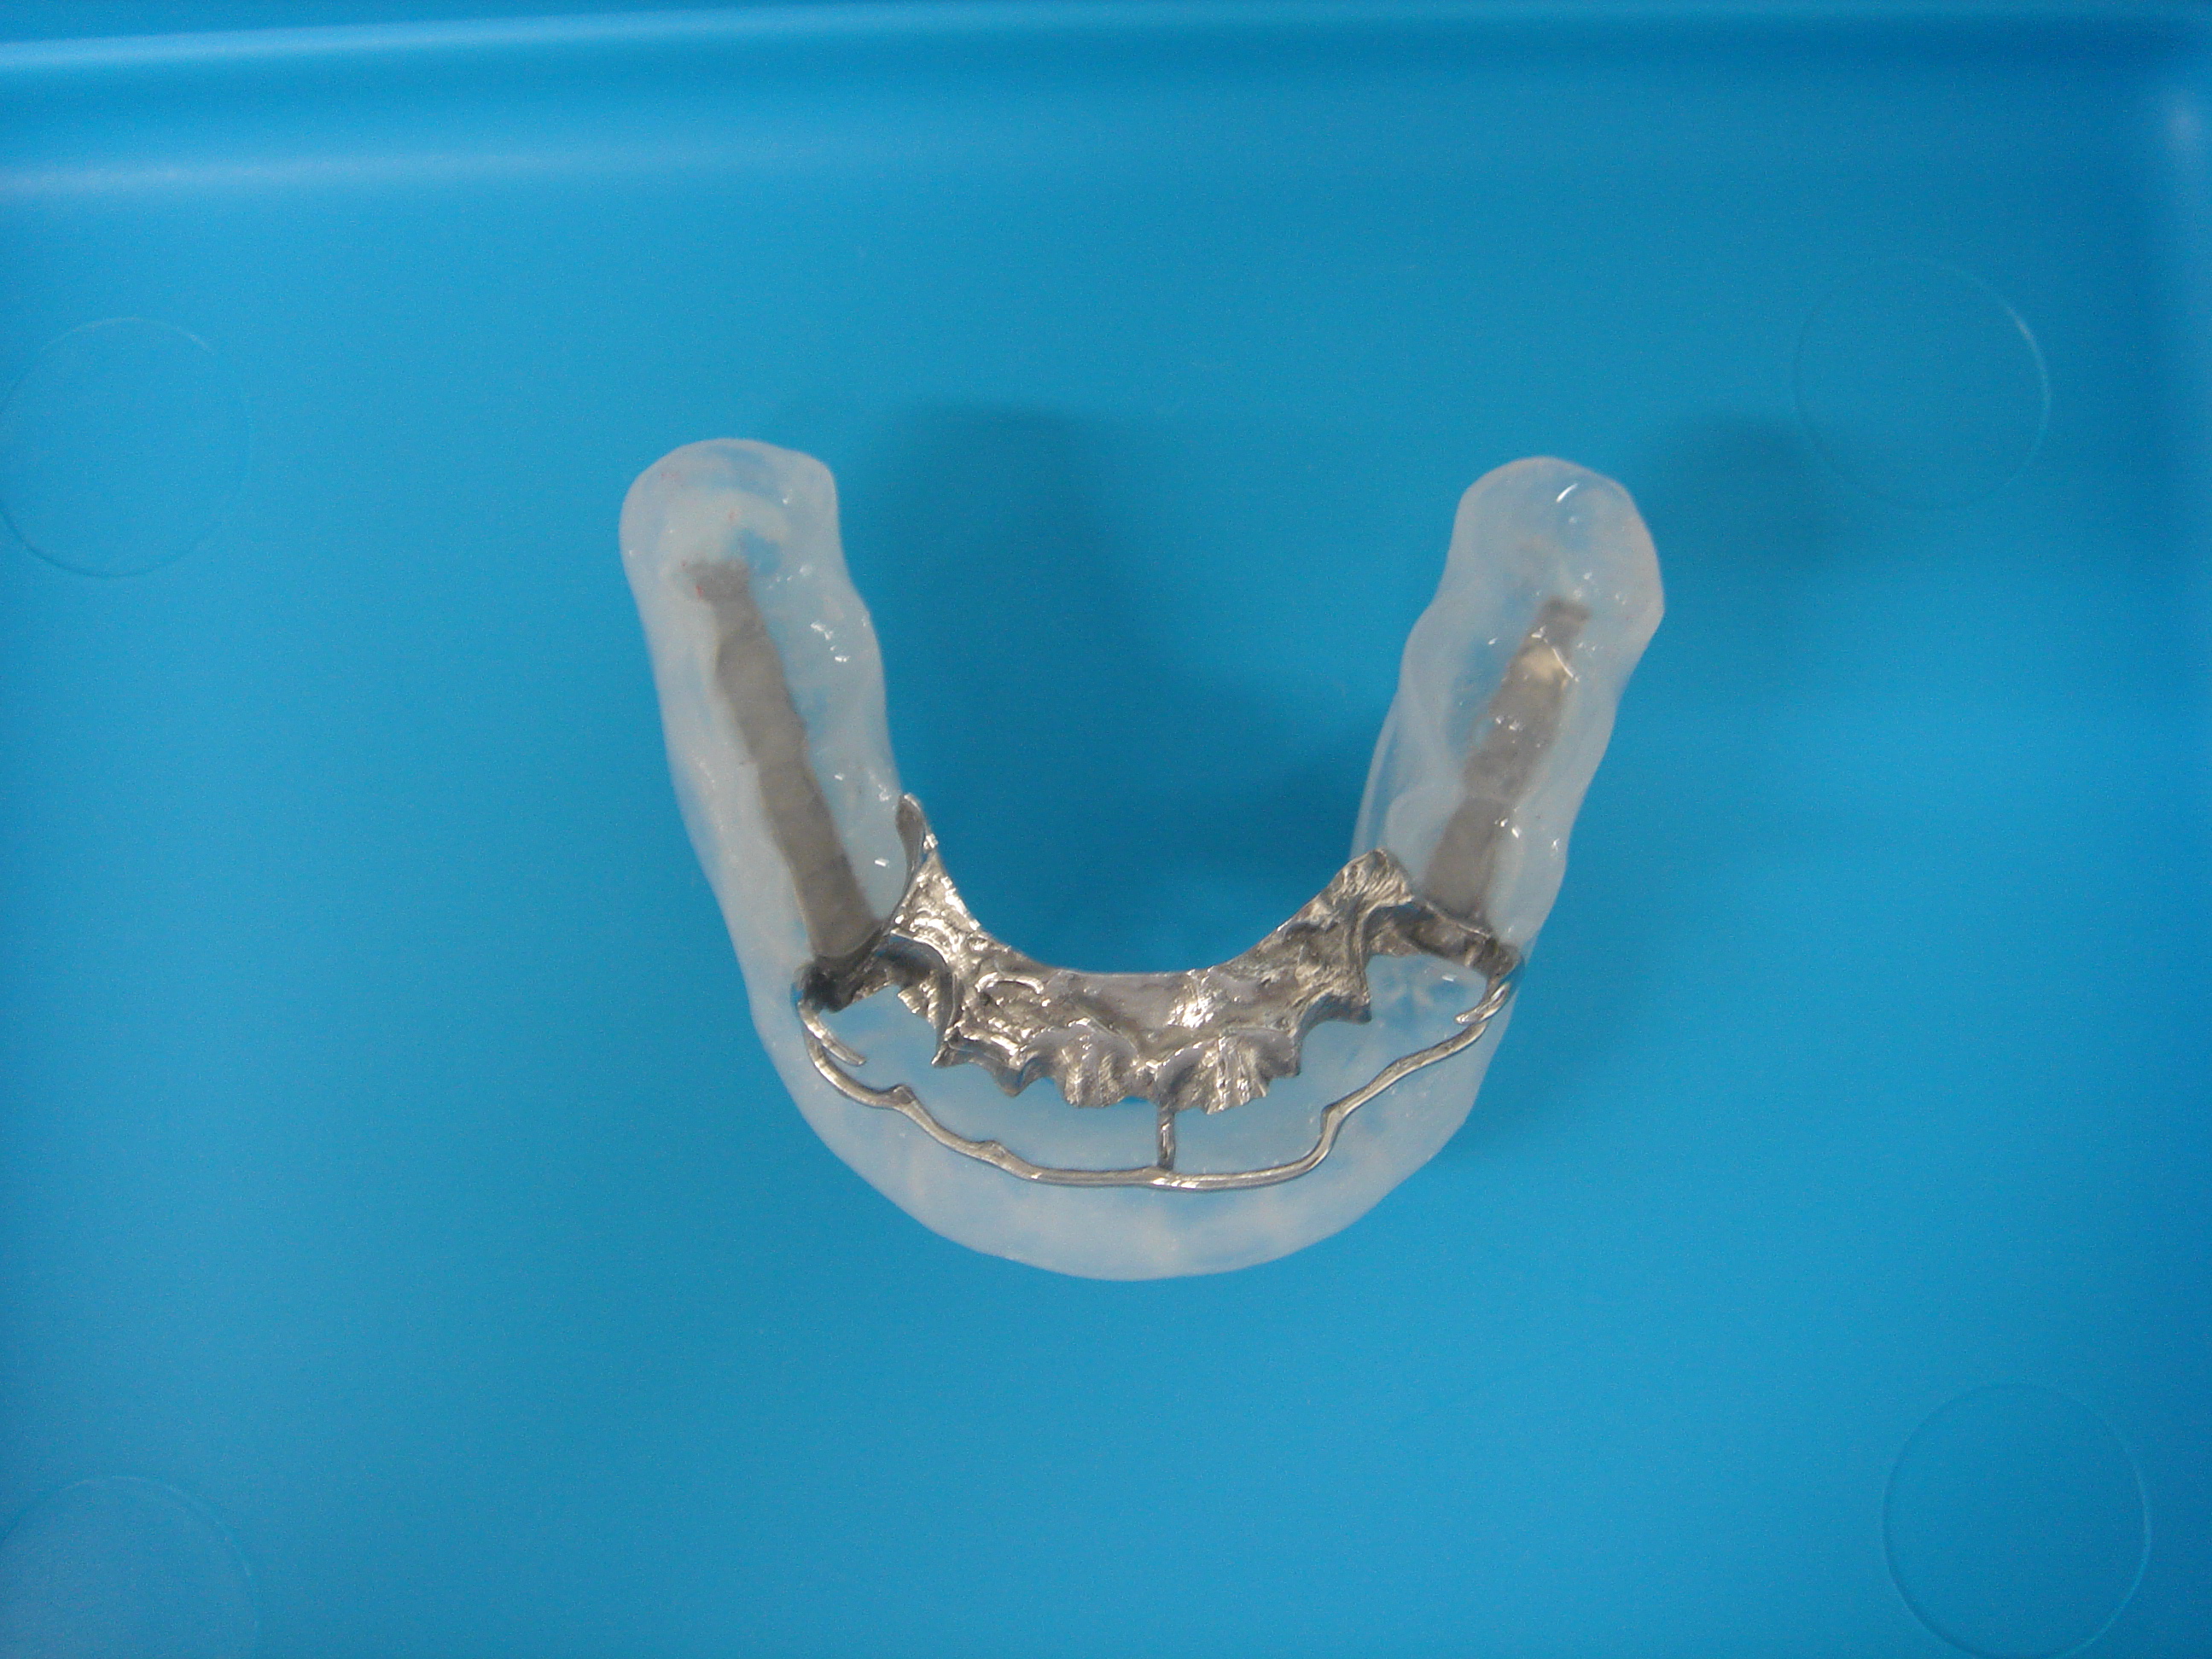

スリープスプリント

成人では軟口蓋(がい)形態異常、扁桃肥大、舌根部肥大、肥満、鼻疾患、甲状腺機能低下症などが原因として多く、睡眠薬、鎮静薬、抗ヒスタミン薬を飲んだり、飲酒、疲労、高い枕、仰臥(ぎょうが)位での睡眠もいびきを増悪させる要因です。治療に際しては、重症度と狭窄部位を確定し、その方法を選択します。対策は、鼻閉の治療、側臥位で睡眠、体重減量、歯科装具(スリープスプリント)を付ける、経鼻的持続陽圧呼吸手術的治療などがあり、特に手術が非常に効果的で、手術法や機器の開発進歩により、外来での手術で改善できる場合もかなり多くなりました。 (いびきの改善手術の3割負担金は29100円です。H.25.12現在。)